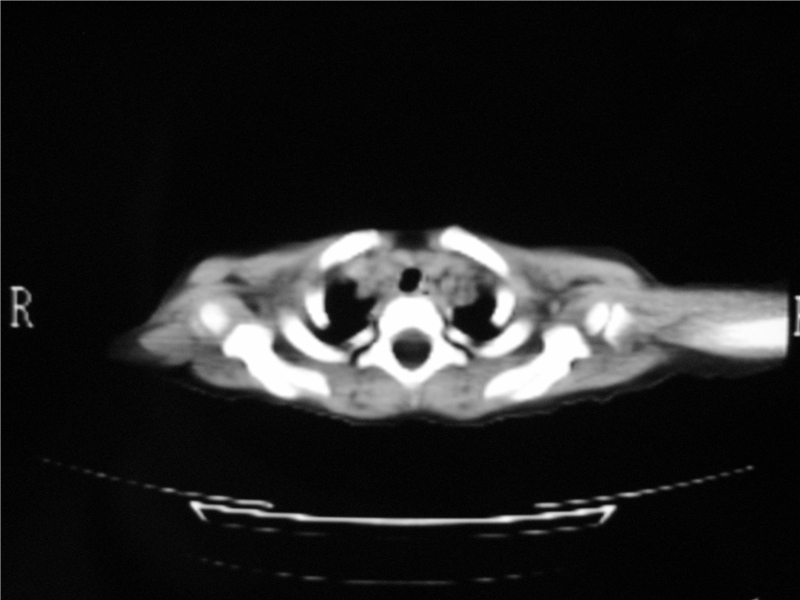

标题: PED3236:男2岁进食花生米后发烧10天。 [打印本页]

标题: PED3236:男2岁进食花生米后发烧10天。

右肺中叶及下叶内段大片实变密度增高影,可见支气管气象,肺炎.

右侧中间段支气管阴性异物可能,建议支气管镜